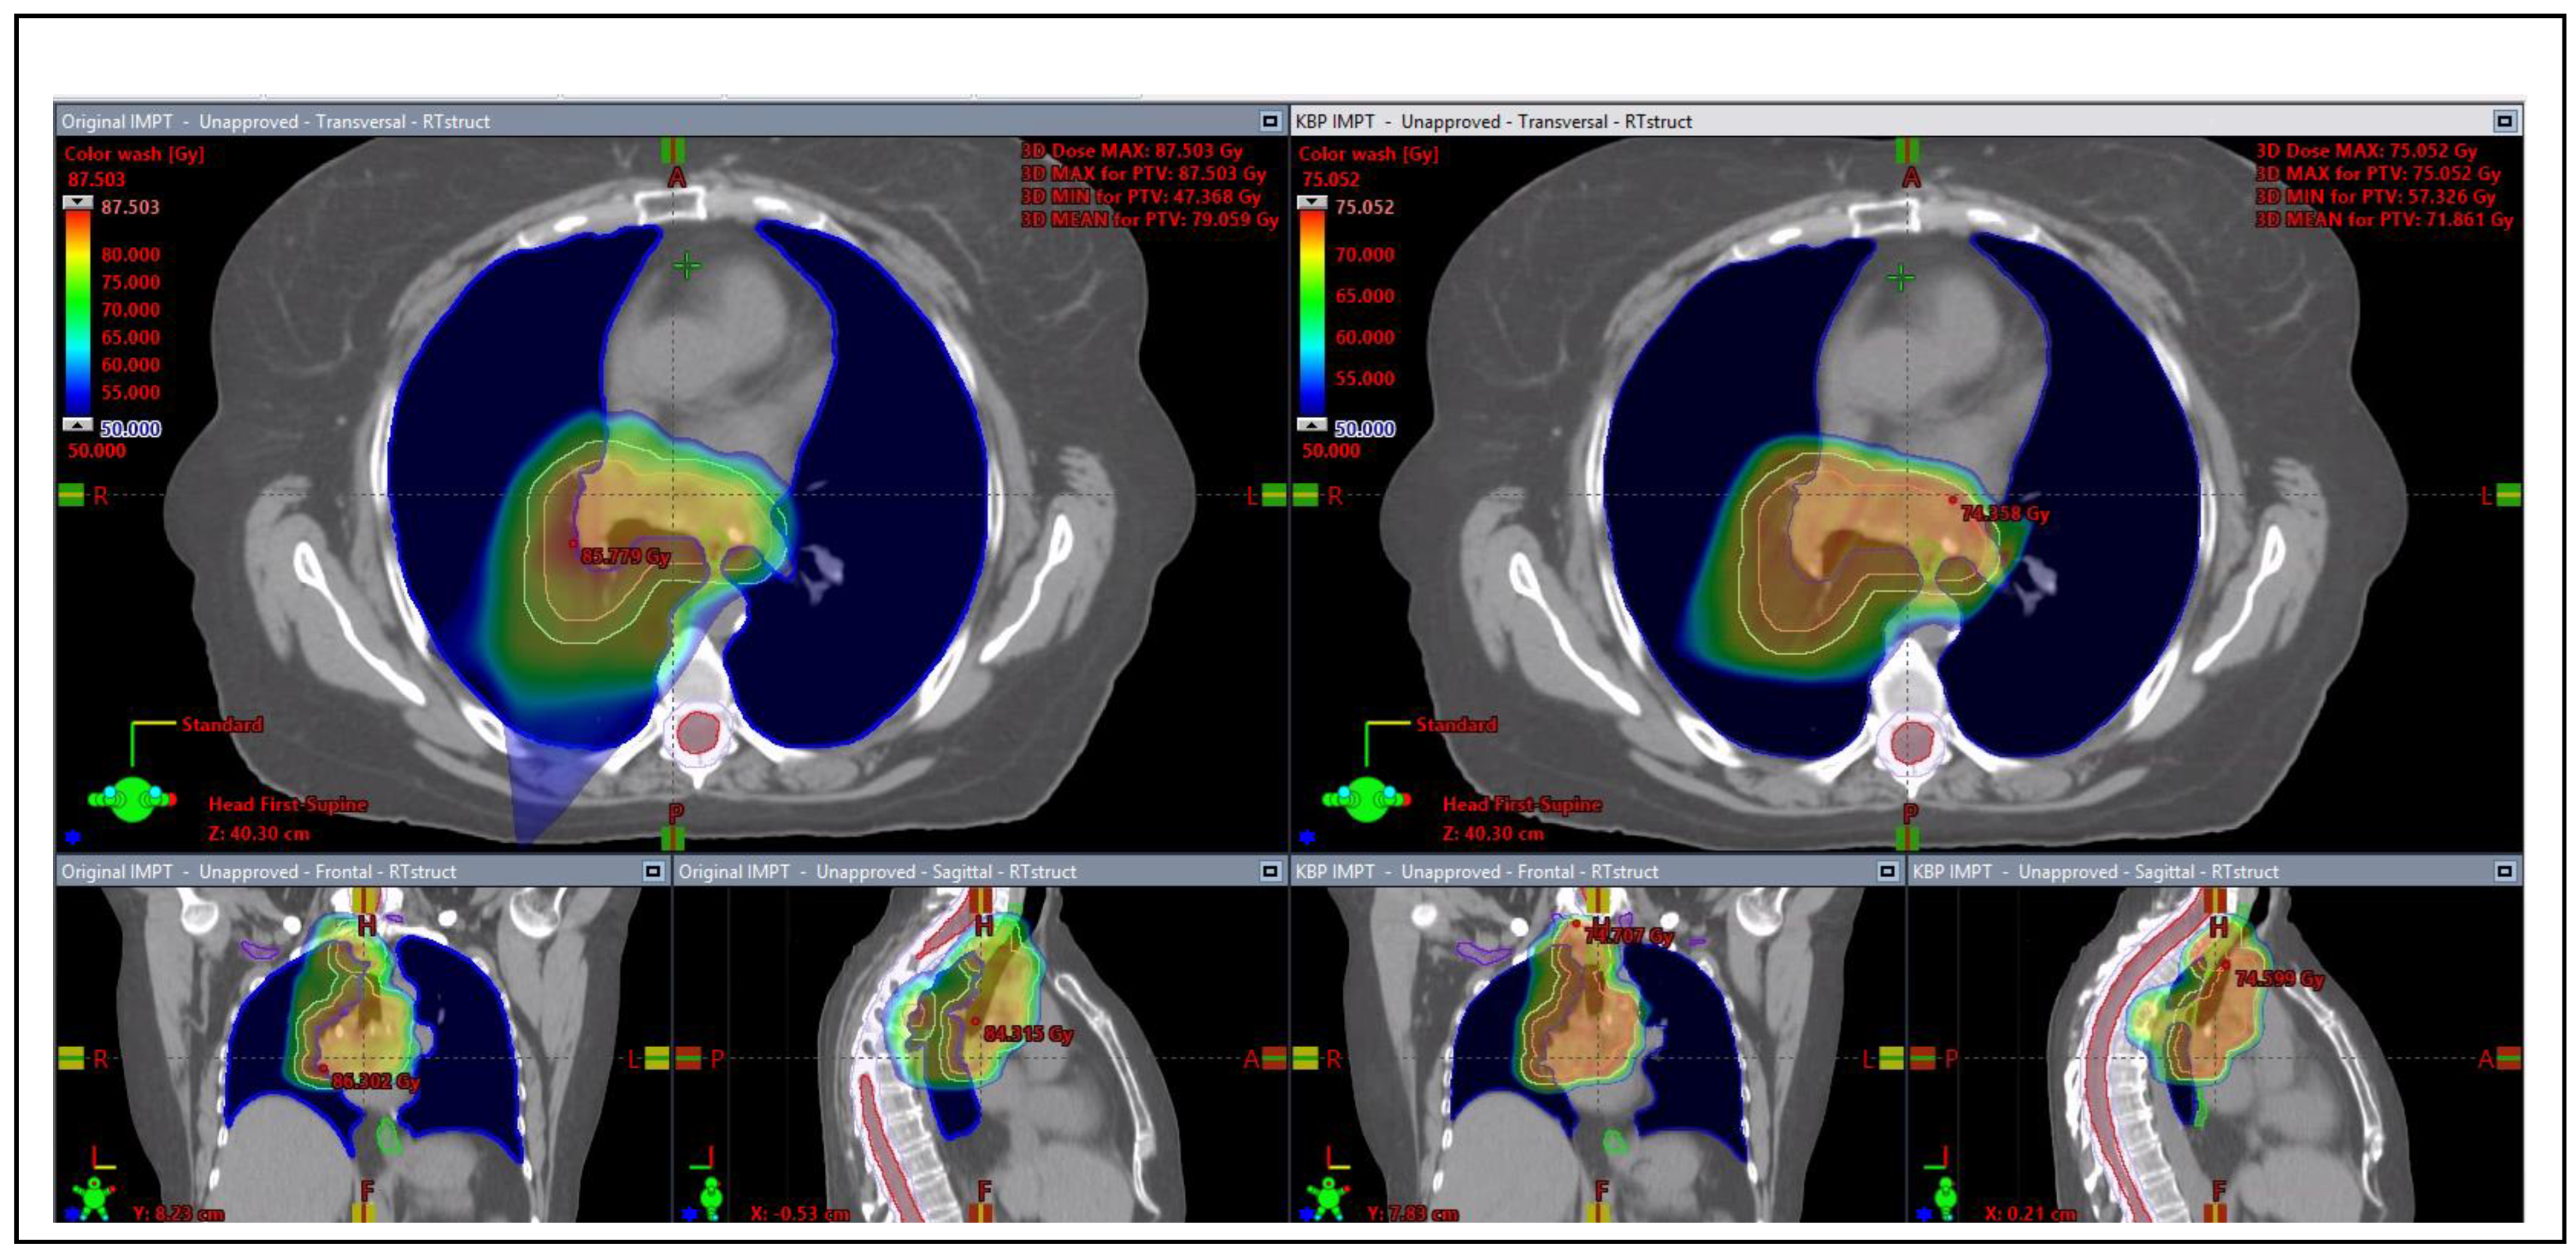

3.3.2. Proton Plan Quality Review

4. Discussions